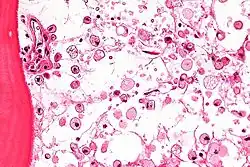

The disease is caused by a defect in the housekeeping gene for lysosomal glucocerebrosidase (also known as beta-glucosidase, EC 3.2.1.45, PDB: 1OGS) on the first chromosome (1q22). The enzyme is a 55.6-kilodalton, 497-amino acid-long protein that catalyses the breakdown of glucocerebroside, a cell membrane constituent of red and white blood cells. In Gaucher disease, the enzyme is unable to function correctly and glucocerebroside accumulates. The macrophages that clear these cells are unable to eliminate the waste product, which accumulates in fibrils and turn into 'Gaucher cells', which appear on light microscopy to resemble crumpled-up paper.[3]